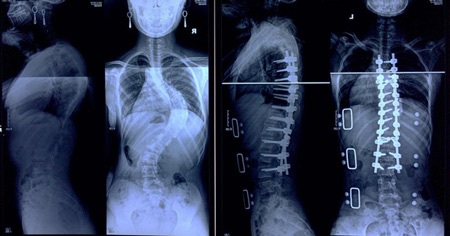

PGS.TS. Nguyễn Văn Thạch, Phó giám đốc Bệnh viện Hữu Nghị Việt Đức, Viện trưởng Viện chấn thương chỉnh hình, Trưởng khoa phẫu thuật cột sống, cho biết vẹo cột sống là sự biến dạng làm cột sống cong từ bên này sang bên kia bao gồm nhiều nguyên nhân: vẹo cột sống bẩm sinh, bệnh lý thần kinh cơ và vẹo cột sống vô căn. Trong đó vẹo cột sống vô căn thường gặp nhất chiếm khoảng 65%, vẹo bẩm sinh chiếm 15% còn lại là 10% do thứ phát của bệnh lý thần kinh cơ.